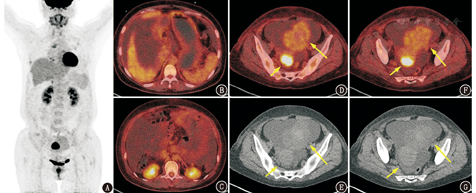

患者女,54岁,主诉腹胀1个月。1个月前患者无明显诱因出现腹胀,伴食量减少,后腹胀逐渐明显,腹围增加。外院腹部B超提示腹盆腔大量积液,盆腔内实性肿物,大小为7.0 cm×6.7 cm,子宫多发肌瘤;腹部增强CT提示左附件区混杂密度影,呈分叶状,增强后不均匀明显强化,考虑卵巢来源可能性大。血清糖类抗原(carbohydrate antigen, CA)125为260.57(正常范围0~35) kU/L,癌胚抗原(carcinoembryonic antigen, CEA)、CA19-9正常。18F-脱氧葡萄糖(fluorodeoxyglucose, FDG) PET/CT显像(图1)可见盆腔内左附件区肿物,呈分叶状,密度不均匀,大部分为软组织密度影,大小为7.4 cm×9.8 cm,中央密度略高,病变代谢活性轻度升高(高于肌肉,略低于肝脏),最大标准摄取值(maximum standardized uptake value, SUVmax)3.7,代谢不均匀,病灶中央密度略增高区为代谢减低区;子宫后壁另见一代谢异常增高的肿物,位于宫体后缘,密度与子宫体相同,大小为3.3 cm×2.4 cm,SUVmax 12.8;此外腹盆腔可见大量积液。在胸部可见双肺胸膜下区多发代谢轻度增高的斑片影。

该例病变较为简单,为单侧附件区占位、子宫体后壁占位、腹盆腔大量积液;双肺内代谢轻度增高斑片影为慢性炎性反应表现,与腹盆腔病变关联不大。考虑到患者为中老年女性,附件肿物和子宫后壁占位、腹盆腔大量积液、血清CA125明显升高这几点支持卵巢原发恶性肿瘤的诊断。但仔细琢磨又有奇怪之处:(1)卵巢癌可有大量腹腔积液,但多见于有种植转移灶的患者(腹膜系统受累),本例除子宫后壁高代谢占位之外,腹盆部并未见明确的种植转移灶。那么子宫后壁高代谢占位有没有可能是转移灶?从位置上看有这种可能性,若子宫后壁的病变是定位在子宫外并与子宫后壁粘连,则子宫后壁的病变也可能是子宫直肠窝的种植转移灶,这里是种植转移的好发部位之一(子宫直肠窝正好处于腹膜反折处,又是重力依赖部位),但子宫后壁占位代谢程度远高于左附件区的病灶,又提示二者不是同一性质的病变。根据子宫后壁病灶的边缘与正常子宫体间是否有夹角(呈锐角或钝角)、两者密度是否有差异等征象可判断病灶在子宫内还是子宫外。本例病灶位于正常子宫体的轮廓内,判断其为子宫内病变的可能性更大,若结合妇科超声、诊断CT、MR可更明确地判断。(2)卵巢恶性肿瘤诸多病理类型中最常见的是上皮来源的卵巢癌,其中又以浆液性和黏液性囊腺癌为主,还有透明细胞癌和子宫内膜样癌等。这些肿瘤的主要影像学特点是囊实性病变(常以囊性成分为主),代谢通常明显增高(若为交界性囊腺瘤代谢可仅轻度增高或不高)。但本例的影像学特点与此并不一致,首先病灶的代谢活性远低于典型的卵巢浆液性和黏液性囊腺癌,若为交界性囊腺瘤,又难以解释为何有大量的腹盆腔积液(通常代表有腹膜转移);另外病灶密度与FDG代谢分布上都比较均质(中央有片状稍高密度影,代谢呈减低区,可能为出血),提示其为实性病变而非囊实性病变。

从左附件区占位的表现来看,卵巢Brenner瘤、卵泡膜纤维瘤、子宫的浆膜下肌瘤或阔韧带肌瘤、低级别肉瘤均可为孤立性的附件区实性肿物,代谢轻度增高或不高。附件区病灶局限,未见明确的周围侵袭或转移,如何解释大量的腹盆腔积液?对于卵巢占位+腹盆腔大量积液,有经验的医师可能会考虑到Meigs综合征。Meigs综合征是指合并胸、腹腔积液的卵巢良性肿瘤,在切除卵巢肿瘤后积液可自行缓解吸收,常见于卵巢Brenner瘤、卵巢纤维瘤和卵泡膜纤维瘤,多见于绝经后女性,其具体发病机制尚不清楚,常伴CA125升高。上述表现与本例的特点相符。子宫后壁代谢增高的占位是否与之相关?实际上子宫后壁的占位与超声提示的子宫肌瘤部位一致。子宫肌瘤多没有明显的代谢活性,有时仅能在CT上看到形态学的改变,如外突、伴钙化灶等,但良性子宫肌瘤的FDG代谢也可以表现为不同程度的代谢增高,标准摄取值(standardized uptake value, SUV)可达10以上[1,2,3,4],目前尚不明确良性子宫肌瘤的代谢增高是否与肌瘤变性等因素相关。另外,子宫肌瘤若发生恶变成为肉瘤,代谢活性同样可以明显升高,这为鉴别子宫肌瘤和肉瘤带来困难。

本例患者最终行子宫双附件切除术,病理为左卵巢卵泡膜纤维瘤,子宫多发平滑肌瘤。看似简单的病例中间可能有不简单的道理,需大胆推测,小心论证。